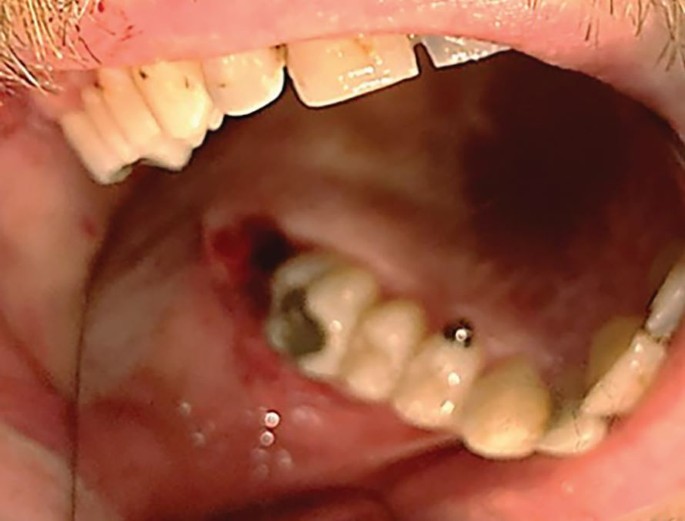

If an oral antral communication is suspected, gently suction over the socket with good light to confirm if present. Never push the suction to the apical region or probe because this risks creating or enlarging a hole or rupturing intact sinus lining which would otherwise aid healing. Performing a Valsalva manoeuvre (a 'nose-blowing' test) is also now contraindicated for the same reasons. If you suspect but cannot confirm an OAC it may be prudent to advise the same post-operative behaviour as if there were an OAC (Fig. 2).

Extraction of the 17 and 18 with the tuberosity attached

Intra oral photograph of the 17, 18 OAC